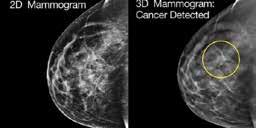

When Karen Stall was diagnosed with breast cancer more than 20 years ago, 3D mammography was not yet a possibility. Today it is not just a possibility, but rather a mandatory standard of practice for health insurers who want to do business in Louisiana. This is in large part thanks to Karen and the non-profit her husband gifted her on the 10th anniversary of her cancer survival journey.

While keeping busy with fund-raising for survivor support efforts for KTSRBI, Karen was also busy “Keeping Abreast” (also the name of the KTSRBI podcast Karen hosts) of current advancements in breast cancer diagnosis. “The best cure for breast cancer is early detection,” Karen said. “When I saw how 3D Tomosynthesis imaging can now make cancer so crystal clear and easy to identify in scans, it was a no-brainer that everyone should have access to such life-saving potential.”

Unfortunately, not all insurance companies would cover the preventative scans even for those who received indeterminant yet worrisome results from regular mammograms and/

or those with a family history of breast cancer.

In 2018 Karen took her efforts in the fight against breast cancer to the State Capitol. She championed the need for 3D Tomosynthesis mammography technology as standard practice for insurers across Louisiana. With the help of legislators including former State Representative Julie Stokes (herself a breast cancer survivor) and now Senator Patrick Connick (a childhood friend of Karen’s), House Bill 460 passed unanimously out of both the House and Senate chambers and became law upon signature by Governor John Bel Edwards. Louisiana is one of only nine states with this standard of care. “It’s nice to have Louisiana at the top of a positive list for once,” she adds.